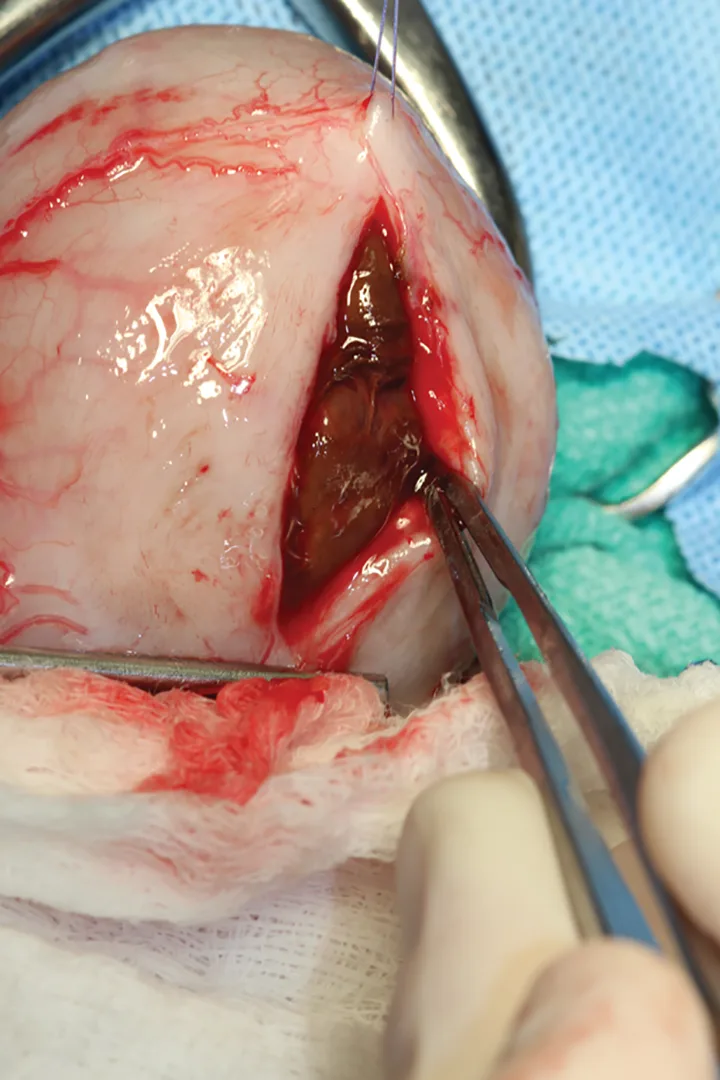

Treatment

Abdominal laparotomy with cystotomy was performed as the patient was no longer azotemic and his PCV had stabilized around 16% after receiving crossmatched packed red cells (Figure 4). The structure was removed and submitted for histopathology. The diagnosis was an organized hematoma; numerous erythrocytes and moderate numbers of neutrophils and macrophages surrounded by a fibrin layer were seen. Cultures of the bladder hematoma and urine were negative.

Figure 4. A 5 cm × 3 cm semifirm, rubbery structure is visible within the urinary bladder.